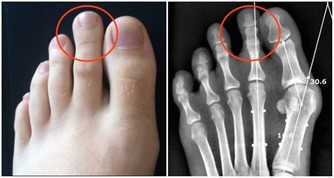

2.增加患病風險睡眠障礙問題以及慢性睡眠不足可增加你患有這些疾病的風險:

心臟疾病,心臟病發作,心臟衰竭,心律不齊,高血壓,中風,糖尿病。據估計,

有九成失眠患者(以難入睡和易醒為特點的人群)還伴有其它一些健康問題。